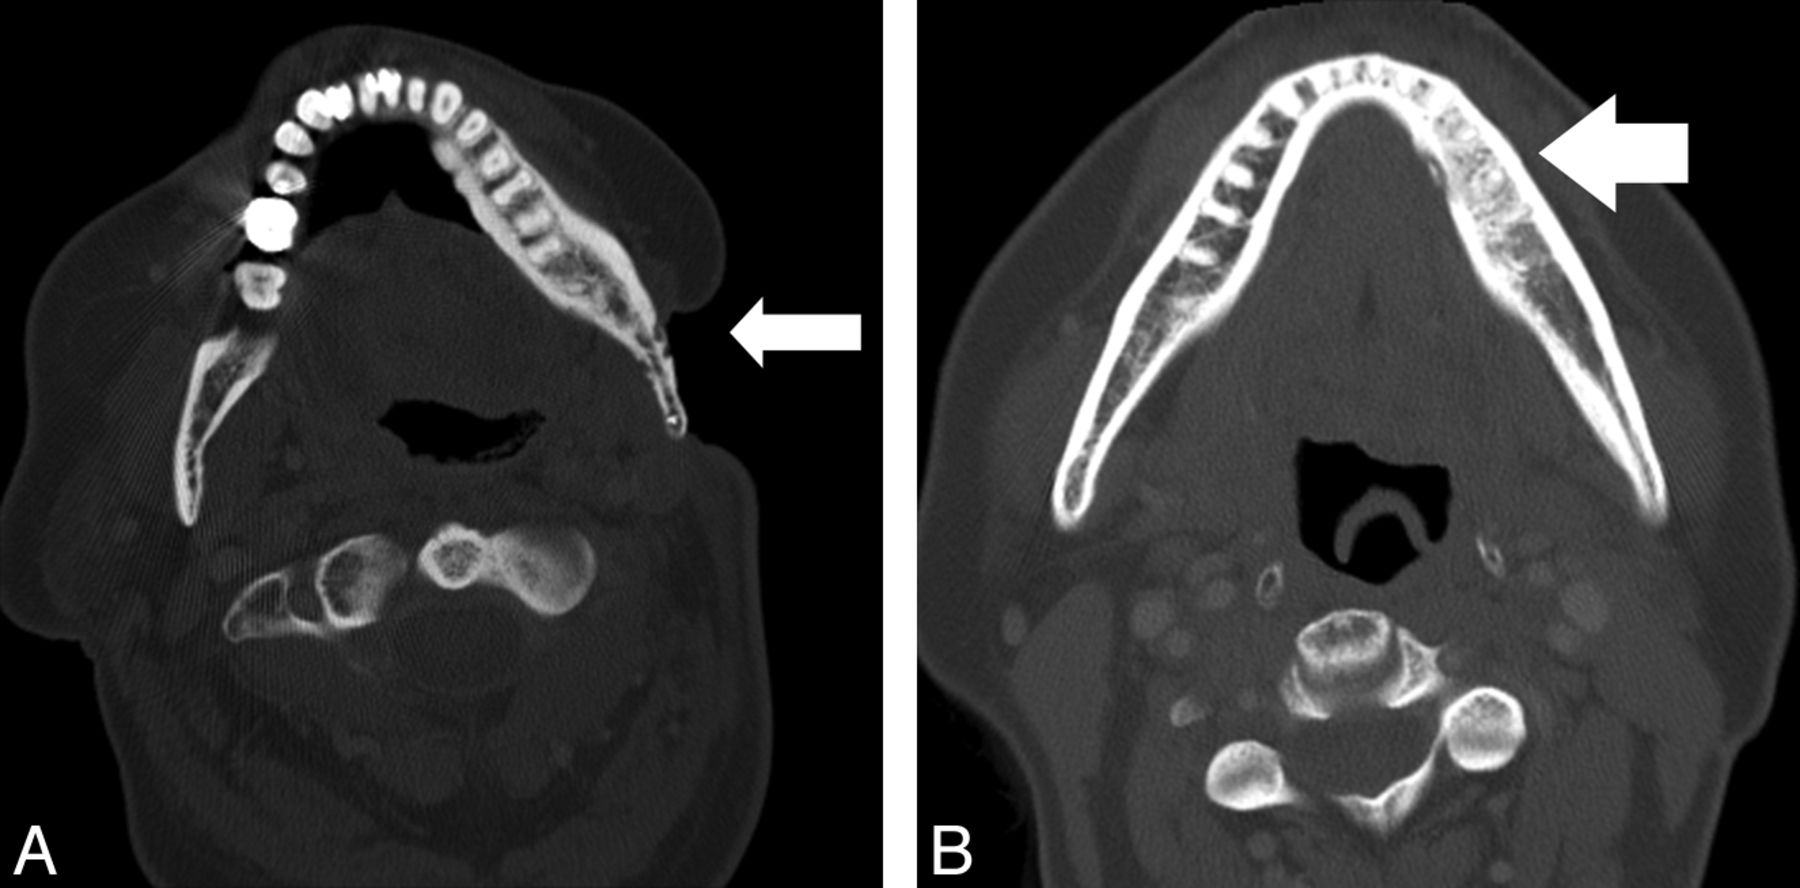

All CT examinations were reviewed retrospectively in random order, separately by 2 Certificate of Added Qualification–certified neuroradiologists (L.A., S.F.), blinded to the clinical findings, the original study interpretation, and the final pathologic diagnosis. Reviewers were asked to comment on the presence or absence of the following imaging findings: 1) a solid measurable mass, 2) a cystic mass, 3) interruption of the cortical margin of the affected bone, 4) fragmentation of the affected bone, 5) loss of trabecula of the affected bone, 6) intraosseous gas in the affected bone, and 7) sclerosis of the affected bone. They were instructed that surrounding inflammatory change (ie, amorphous soft-tissue stranding or infiltration) and muscle or tissue thickening (Fig 1A, -B) did not qualify as a solid mass and that a discrete measurable mass (Fig 2) must be present. They were further asked to measure the size of any solid or cystic mass (Fig 2E, -F), and in those cases in which trabecular loss existed, they were asked to classify the pattern of trabecular loss as either permeative or lucent. They were instructed that a permeative pattern indicated multiple, independent focal lucent lesions, which, in sum, did not account for >75% loss of total bone trabecula (Fig 3A). A lucent pattern was defined as >75% loss of total bone trabecula in the area of abnormality (Fig 2C, -D). Radiologists were also asked to record the area or areas of the mandible affected, with choices being either the right or left mandibular condyle, coronoid process, ramus, angle, or body.

Images from 2 different patients with soft-tissue findings of osteoradionecrosis. A, Axial CT scan (soft-tissue window) shows enlargement and thickening of the musculature of the right masticator space (white arrowheads), without evidence of a distinct measurable mass, adjacent to an area of osteoradionecrosis. B, Axial CT scan (soft-tissue window) shows inflammatory thickening of soft tissues (white arrow) adjacent to an area of osteoradionecrosis involving the right mandibular body.